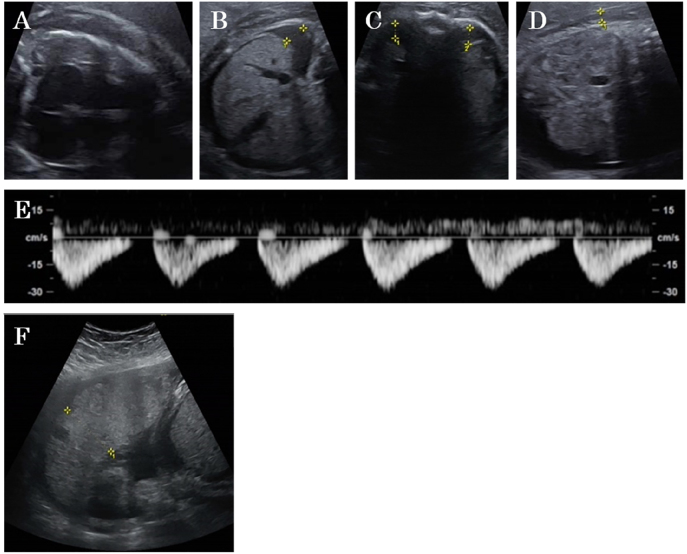

Case presentation: A 37-year-old pregnant woman underwent emergency cesarean delivery at 34 weeks' gestation due to rapidly progressive fetal hydrops leading to fetal dysfunction, resulting in neonatal death. Placental pathology indicated multiple placental giant chorangiomas that occupied 40% of the placenta. Because of the disk shape of the placenta, prenatal diagnosis by ultrasonography was difficult.

Conclusions: Some placental chorangiomas are difficult to diagnose and lead to fetal hydrops and poor prognosis, even if ultrasonography does not show an obvious mass in the placenta.